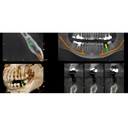

The cutting-edge CS 8200 3D panoramic and cone beam system from Carestream Dental delivers powerful versatility and precision all in one innovative package.

This next-gen model expands your field of view options for unparalleled flexibility. With nine selectable views ranging from 4x4 cm all the way up to 12x10 cm, the CS 8200 is equipped to cover virtually any diagnostic need your practice requires.

The CS 8200 3D blends 2D panoramic technology, CBCT imaging and 3D model scanning to create one powerful unit.

The CS 8200 3D offers multiple fields of view, to support all of your diagnostic needs — from routine exams to specialized ones.

This all-in-one unit is designed to seamlessly capture stunning 2D panoramic views and medium field of view 3D cone beam scans with ease. With a wide range of medium to large field of view settings from 4x4 cm up to 12x10 cm, the CS 8200 supports an impressive variety of specialized dental applications.

Whether you need detailed bitewing analysis, full jaw visualization, or targeted higher resolution imaging, this system's adaptable field of view has you covered. And as your practice grows, simply upgrade to add cephalometric capabilities for even greater clinical flexibility.